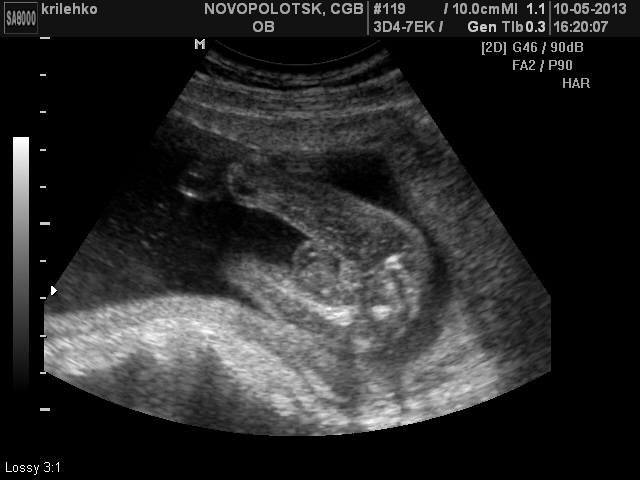

у нас пацан, и как-то вообще по другому было...ракурс как на 1 снимке, только ножки пождаты... так вот там были 2 булки побольше, потом 2 шарика поменьше и стрючочек)))) но как говорит узист: "Вижу 100 % мальчик, но точнее только при родах"... узи так-то может и ошибаться, видела прикол в роддоме, когда на сохранении лежала, выписывали ребеночка в ярко голубом конверте с ярко розовой ленточкой) так что тут уж 100 % результат точно только при родах))))

Мальчик))) У меня девчонка, по другому там все выглядит с такого ракурса)))

спасибо большое а врач написал пол женский но во мне что червяк сомнений)))мне 3 раза снился мальчик))и пузик я свой называю как мальчика само вырывается))она так и не могу сказать)))

Ну, если судить по 1-му снимку, то поцан точно))) А вы мальчика хотите?